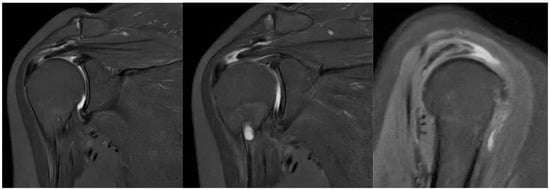

At six months after the surgery, a new MRI was performed, showing the reaction induced by the implant, with the progressive formation of tendon-like tissue (Figure 9).

Figure 9.

Postoperative MRI at 6 months after surgery, showing progressive formation of new tendon-like tissue with improvement of tendon thickness.

The effects of biological augmentation are evident in histologic studies and MRI. After 6 months, there is no histological evidence of the Regeneten implant remaining and the neotendon is indistinguishable from the native tendon on MRI, both in partial tears treated with isolated bioinductive repair and in full-thickness tears managed with complete augmented repair [5]. Schlegel et al. found that 87% of partial tears treated solely with bioinductive repair using Regeneten showed more than a 50% reduction in tear size in MRI after 24 months, along with a significant increase in tendon thickness. Additionally, no significant differences in clinical outcomes, tear healing, or tendon thickness were observed based on the location of the tear [7,19].

The subjective improvements and the improvements in the range of motion and tendon regeneration observed in this case are encouraging and suggest that the bioinductive implant may have contributed to enhanced healing. While a direct comparison with patients undergoing mechanical repair alone is not possible in this case report, the observed outcomes appear comparable to, or potentially better than, those reported in studies evaluating traditional repair techniques. Specifically, the patient achieved a near-full range of motion and a significant reduction in pain at 6 months post-surgery, which is a positive outcome. The observed outcomes in this case are consistent with the manufacturer’s reported data for the Regeneten implant, which indicate that the implant can promote tendon healing and improve clinical outcomes in patients with rotator cuff tears. Specifically, Smith and Nephew reports that Regeneten reduced the size of partial-thickness rotator cuff tears by over 50% in all tear locations [7]. The positive results observed in this case further support the use of Regeneten for the augmentation of rotator cuff repair. However, further research is needed to directly compare the outcomes of bioinductive implants with mechanical repair alone and other augmentation techniques.